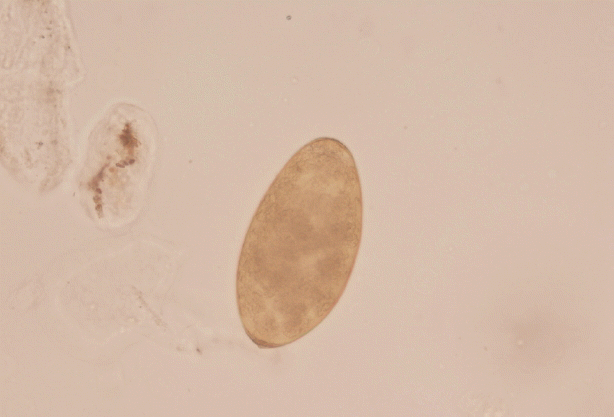

In June 2016, detailed clinical, laboratory, and radiographic tests were performed in Fuzhou General Hospital of Nanjing Military Region, Nanjing, China. Laboratory tests revealed high eosinophilia, mild normocytic normochromic anemia, and high serum activity of alkaline phosphatase (ALP), with normal alanine aminotransferase (ALT) and aspartate amino transferase (AST) levels. MRI showed hypodense changes (total diameter up to 6 cm) in both liver lobes below the diaphragm, predominantly localized posteriorly and centrally (Fig. 1).

Migration of juvenile Fasciola through the liver in the invasive stage could cause hepatic lesions. Pathological sections show micro-abscesses and tunnel-like areas of parenchymal necrosis [31]. Imaging should be applied as auxiliary diagnosis, which may show abscesses and tunnels caused by the migrating young flukes or those in the biliary passage (chronic infection) [32]. The abdominal MRI finding in the current patient showing hypodense clustered lesions on the periphery of both hepatic lobes was compatible with the hepatic phase of fascioliasis. However, images seen on ultrasound and CT may sometimes be confused with malignancy or stones. The most useful diagnostic test for detecting the bile ducts is cholangiography by endoscopic retrograde cholangiopancreatography (ERCP). ERCP is quite important in evaluating symptomatic patients, especially in those with cholestatic syndrome, colicky pain, and abnormal liver function, or those in whom the parasitic disease has caused systemic involvement [33].

Fig. 1

Abdominal magnetic resonance imaging (MRI) showing multiple hypodense foci with subcapsular location.

Fig. 1 Abdominal magnetic resonance imaging (MRI) showing multiple hypodense foci with subcapsular location.